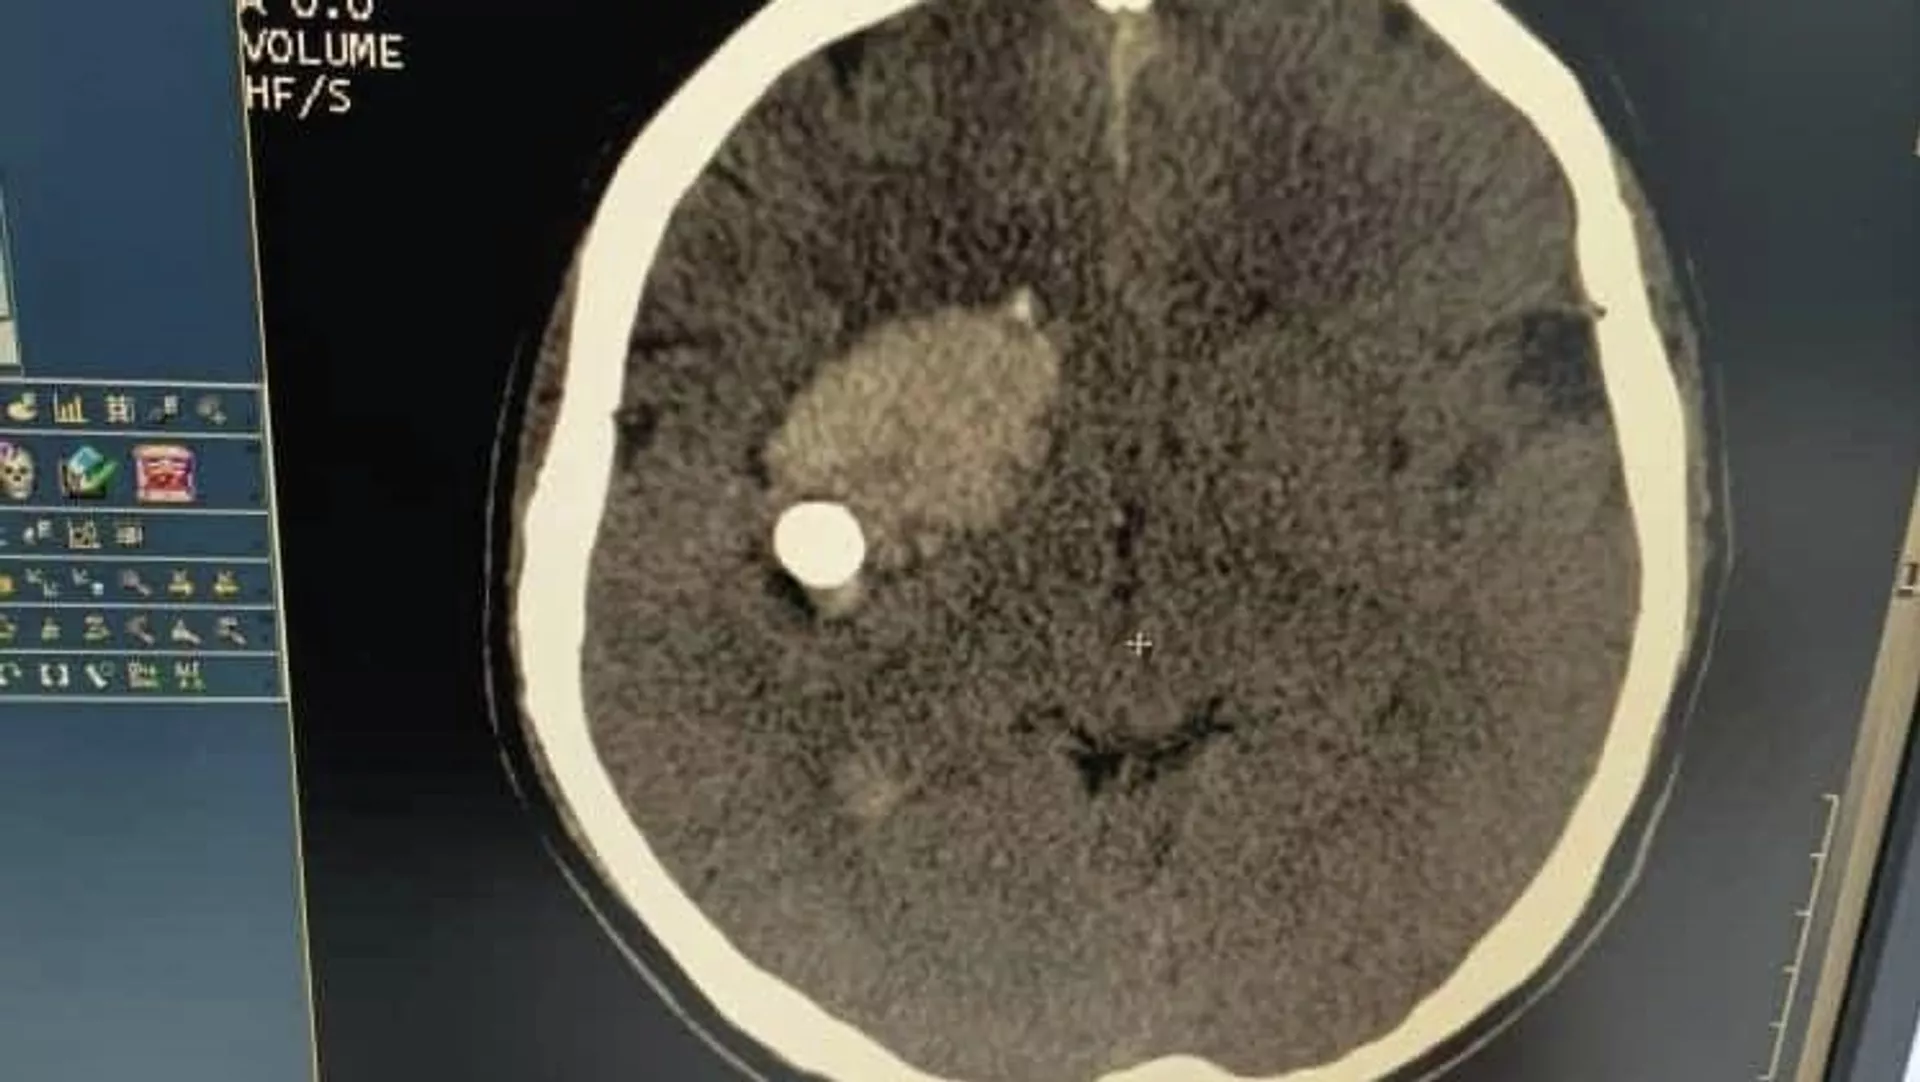

Пациента с пулей в мозге спасли кыргызстанские врачи

БИШКЕК, 10 фев — Sputnik. Кыргызстанские врачи успешно прооперировали пациента с пулей в голове.

Как сообщила пресс-служба Министерства здравоохранения, сложную операцию на мозге провели вчера в Джалал-Абадской областной больнице. Пациента спасли заведующий нейрохирургическим отделением Абдибайит Идирисов и его команда. Сейчас состояние пострадавшего стабильное.

В Минздраве сообщили, что мужчина поступил с открытым пулевым ранением головы. Кто в него стрелял, пока неизвестно.